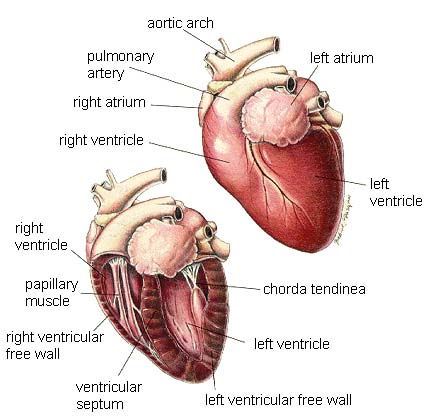

The cardiovascular system includes the heart and blood vessels. The cardiovascular system performs the function of pumping and carrying blood to the rest of the body. The blood contains nutrients and oxygen to provide energy to allow the cells of the body to perform work.